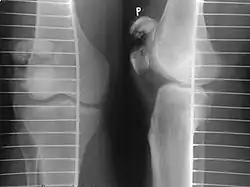

Some people have a normal bipartite patella or two-part patella which can appear as a fracture. The fragment is usually seen in the top outer corner of the patella and can be distinguished from a fracture by being present in both knees.[6]